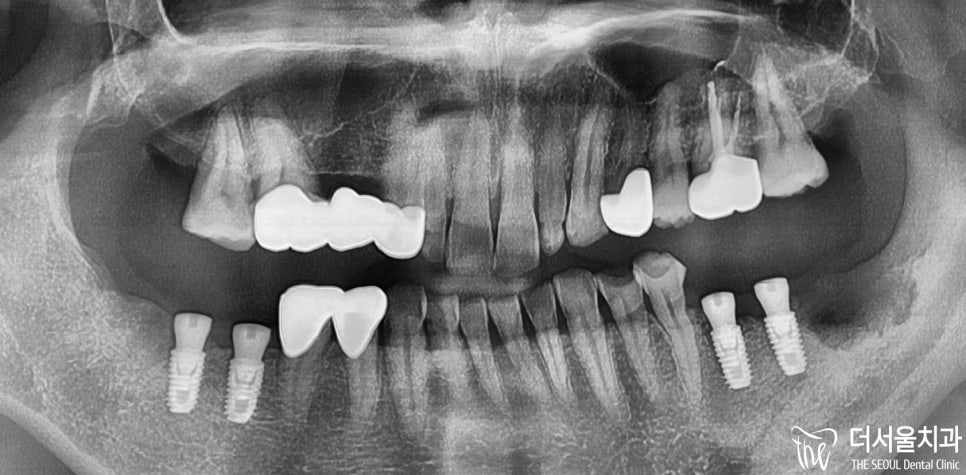

『첫 진료』

처음 더서울 수정구치과 를 내원해주셨을 때,

구강 내 상태는 이러했습니다.

우선 윗니를 살펴보면,

14, 15번 어금니 는 상실되었습니다.

또, 24번은 아예 이가

깊숙히 패여있는 것을

확인할 수 있었죠.

아랫니 또한 마찬가지였습니다.

36,46번 어금니 모두 상실했고,

36번에는 잔존 치근 잔해만

남아있었는데요.

전반적으로 좋지 않았습니다.

곳곳에 파절 및 마모된 것들이 많아서

서둘러 해결하지 않으면,

많은 치아 를 잃게 될 가능성이 높죠.

여기서 그치지 않고

수정구치과 는 좀 더 자세히 파악하려

파노라마 엑스레이 촬영을 했는데요.

실제 구강 속을 살펴봤을때도

그리 좋지 않았었는데,

파노라마로 보면 더하네요…

특히 37, 38번 뿌리 부분에

시커멓게 변해버린 것을 볼 수 있죠?

이미 염증 이 심하다는 것을

확실히 보여주고 있으며,

치아 고정력이 떨어져

심하게 흔들리고 있었습니다.

그리고 오랜 시간 방치해서 그런지

치아 들이 옆으로 쓰러져 공간이

부족하다는 것을 확인할 수 있습니다.